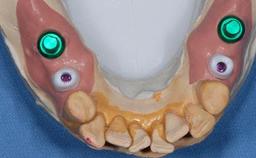

Abutment Type Customized

Prosthesis Type FDP

Retention Cemented, with meso-structure Cemented, with meso-structure